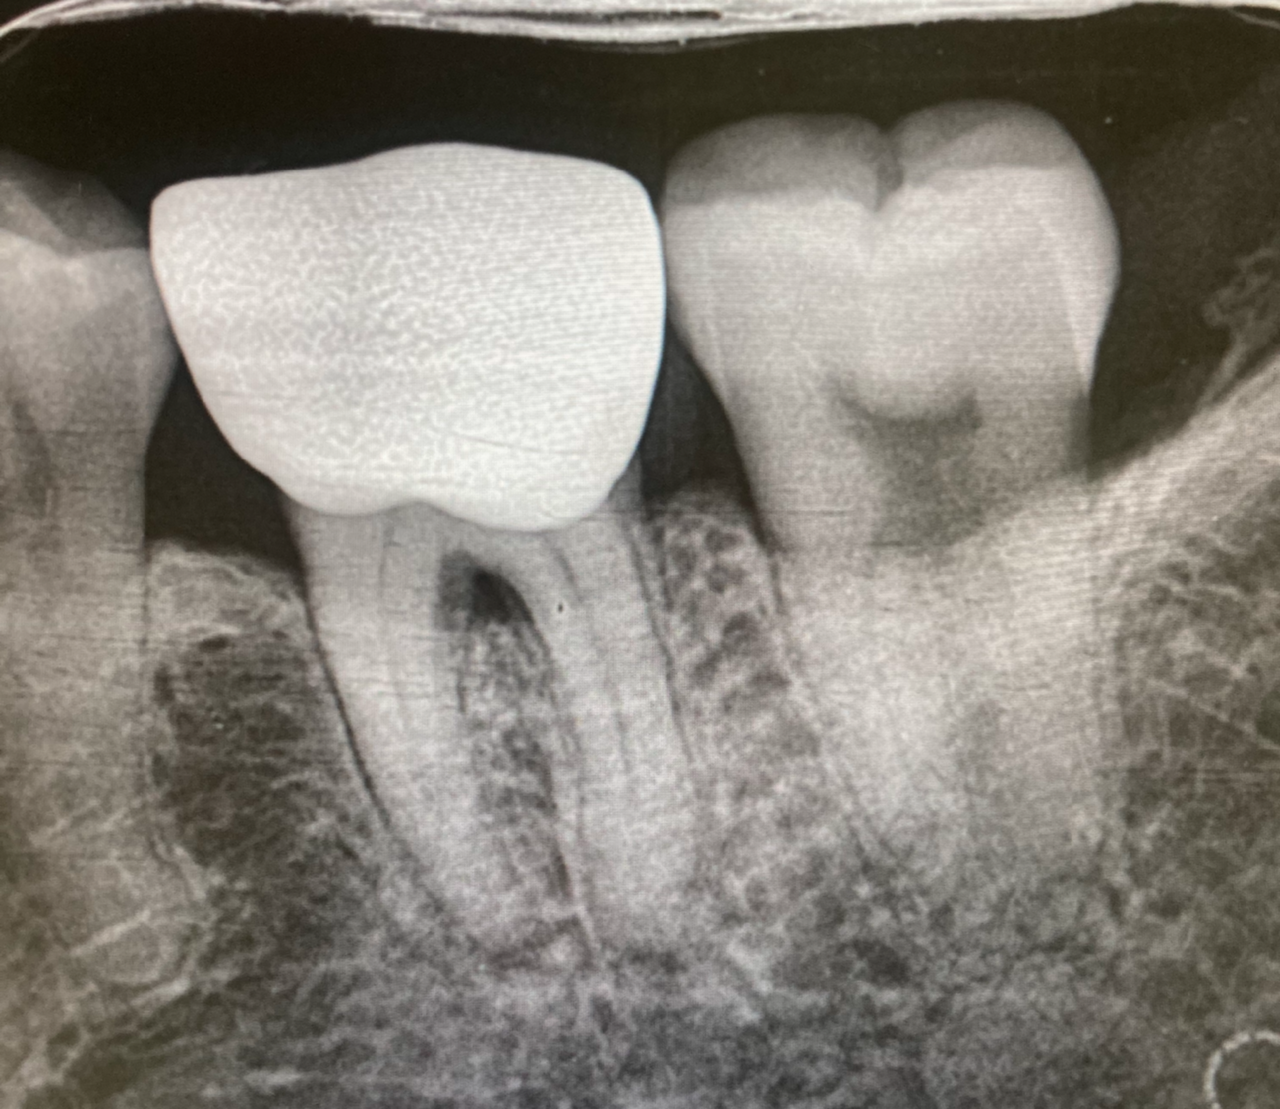

여차저차 설명을 하니 엑스레이 사진도 찍고 전기검사도 하고 찬물검사도 했다. (하지만 아픈 반응은 없었다.) 뿌리 끝 쪽이 확실하진 않지만 염증이 있는 것 같다고 하며 나에게 나이 많으신 분한테 크라운 받은 거냐고 물으시며 어쩌다 치료를 받게 된 거냐고 묻길래 몇 달 전에 아빠한테 받은 거고 신경치료까진 안 해도 된다고 해서 크라운을 받았고 이제는 치료를 안 하셔서 여기 온 거라고 했다.

아니면 아프면 가족이라 바로 또 치료해 줄 수 있으니 굳이 신경치료를 안하는걸까? 그래서 나는 이제까지 신경치료를 받아본 건지 안 받아본 건지도 몰랐다. 여기서 엑스레이로 이 전체를 찍어보더니 신경치료 안 받아보셨다며 자세히 설명을 해주셨다. 해놓은 크라운은 없애고 가운데를 구멍을 낸 뒤 신경을 제거하고 고무관을 넣은 뒤 레진으로 메꾸고 새 크라운을 씌운다고 하신다. 가격은 45-50만 원.

아빠는 크라운을 뚫어서 신경치료를 해달라고 해보라고 한다. 그렇게 임시로 몇 달 있다가 새 걸로 바꾸면 된다고. 엑스레이 사진을 아빠가 볼 수 없냐고 한다. 나는 영 눈치가 보여서 그게 좀 그렇다고 했더니 당당하게 물어보라며 왜 그러냐고 한다. 그리고 일반 진통제말고 소염제사서 먹으면 나을 거라고 한다. 신경치료한다고 해서 안 아픈 것도 아니고 지금 염증있는지 확실한 것도 아니라고. 2-3일 먹어보고 계속 아프면 그때 다시 하면 된다고.

슬쩍 찍은 사진을 아빠에게 보냈더니 이가 좀 들떴다며 조금 갈아내서 위아래 교합을 맞추면 안 아플 거라고 하신다. 약국에서 소염제를 샀다. 집 가서 먹어야지. 먹었더니 괜찮아지는 것 같기도하다.